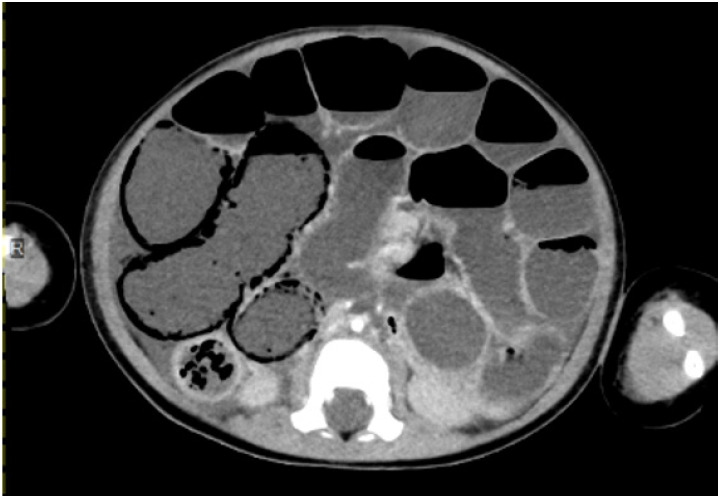

While nonocclusive mesenteric ischemia (NOMI) has been reported in a significant percentage of adults who were resuscitated after cardiac arrest, it is rare in children. This report presents the first known Japanese case of pediatric NOMI after return of spontaneous circulation following cardiac arrest. A 16-month-old boy experienced cardiac arrest due to asphyxiation from foreign bodies in the airway. After receiving 10 doses of adrenaline, with a maximum arrest time of 95 minutes, the patient achieved return of spontaneous circulation. However, 40 hours after onset, the patient developed NOMI, resulting in refractory hypotensive shock with decreased blood pressure, distended abdomen, and increased intravesical pressure. The patient was successfully rescued with two laparotomies and was discharged. Although NOMI is uncommon in children, appropriate treatment can be lifesaving.